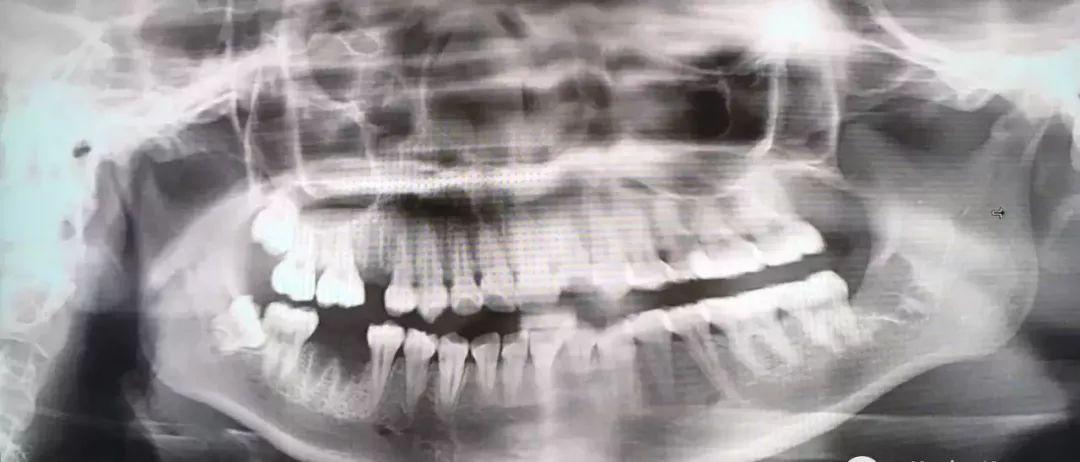

后介紹一下,牙根彎曲,騎在下頜管上的智齒...由于下頜管內(nèi)神經(jīng)豐富,拔除的時(shí)候需要極度小心,而且看長(zhǎng)相也知道這種模式的拔牙,難也貴!

也是先切開(kāi)牙肉,翻開(kāi)并露出骨頭,切下牙冠后取出,再處理下面的牙根。

把牙根分成兩半,根據(jù)牙根的走向,分別小心地撬出來(lái),這個(gè)過(guò)程十分考驗(yàn)技術(shù),要謹(jǐn)慎避免損傷到下頜神經(jīng)...